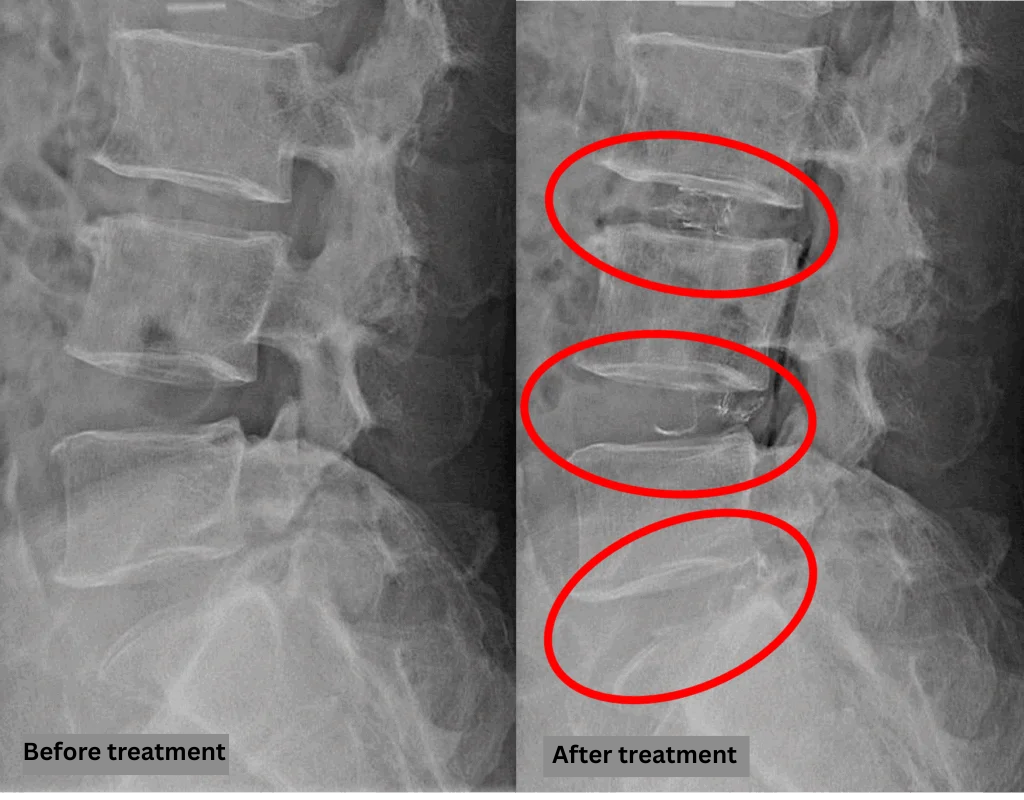

- L3/4: Disc degeneration, bulging, foraminal stenosis, spinal canal stenosis

- L4/5, L5/S1: Disc degeneration, bulging, foraminal stenosis

The above findings were also observed on the imaging.

Based on imaging, spinal canal compression due to disc findings at L3/4 was considered the most likely cause of symptoms.

Although the disc findings at L4/5 and L5/S appear to contribute little to the current symptoms, they have potential for future impact.

After consulting with the patient, the Cellgel Method was performed on L3/4, 4/5 and 5/s.